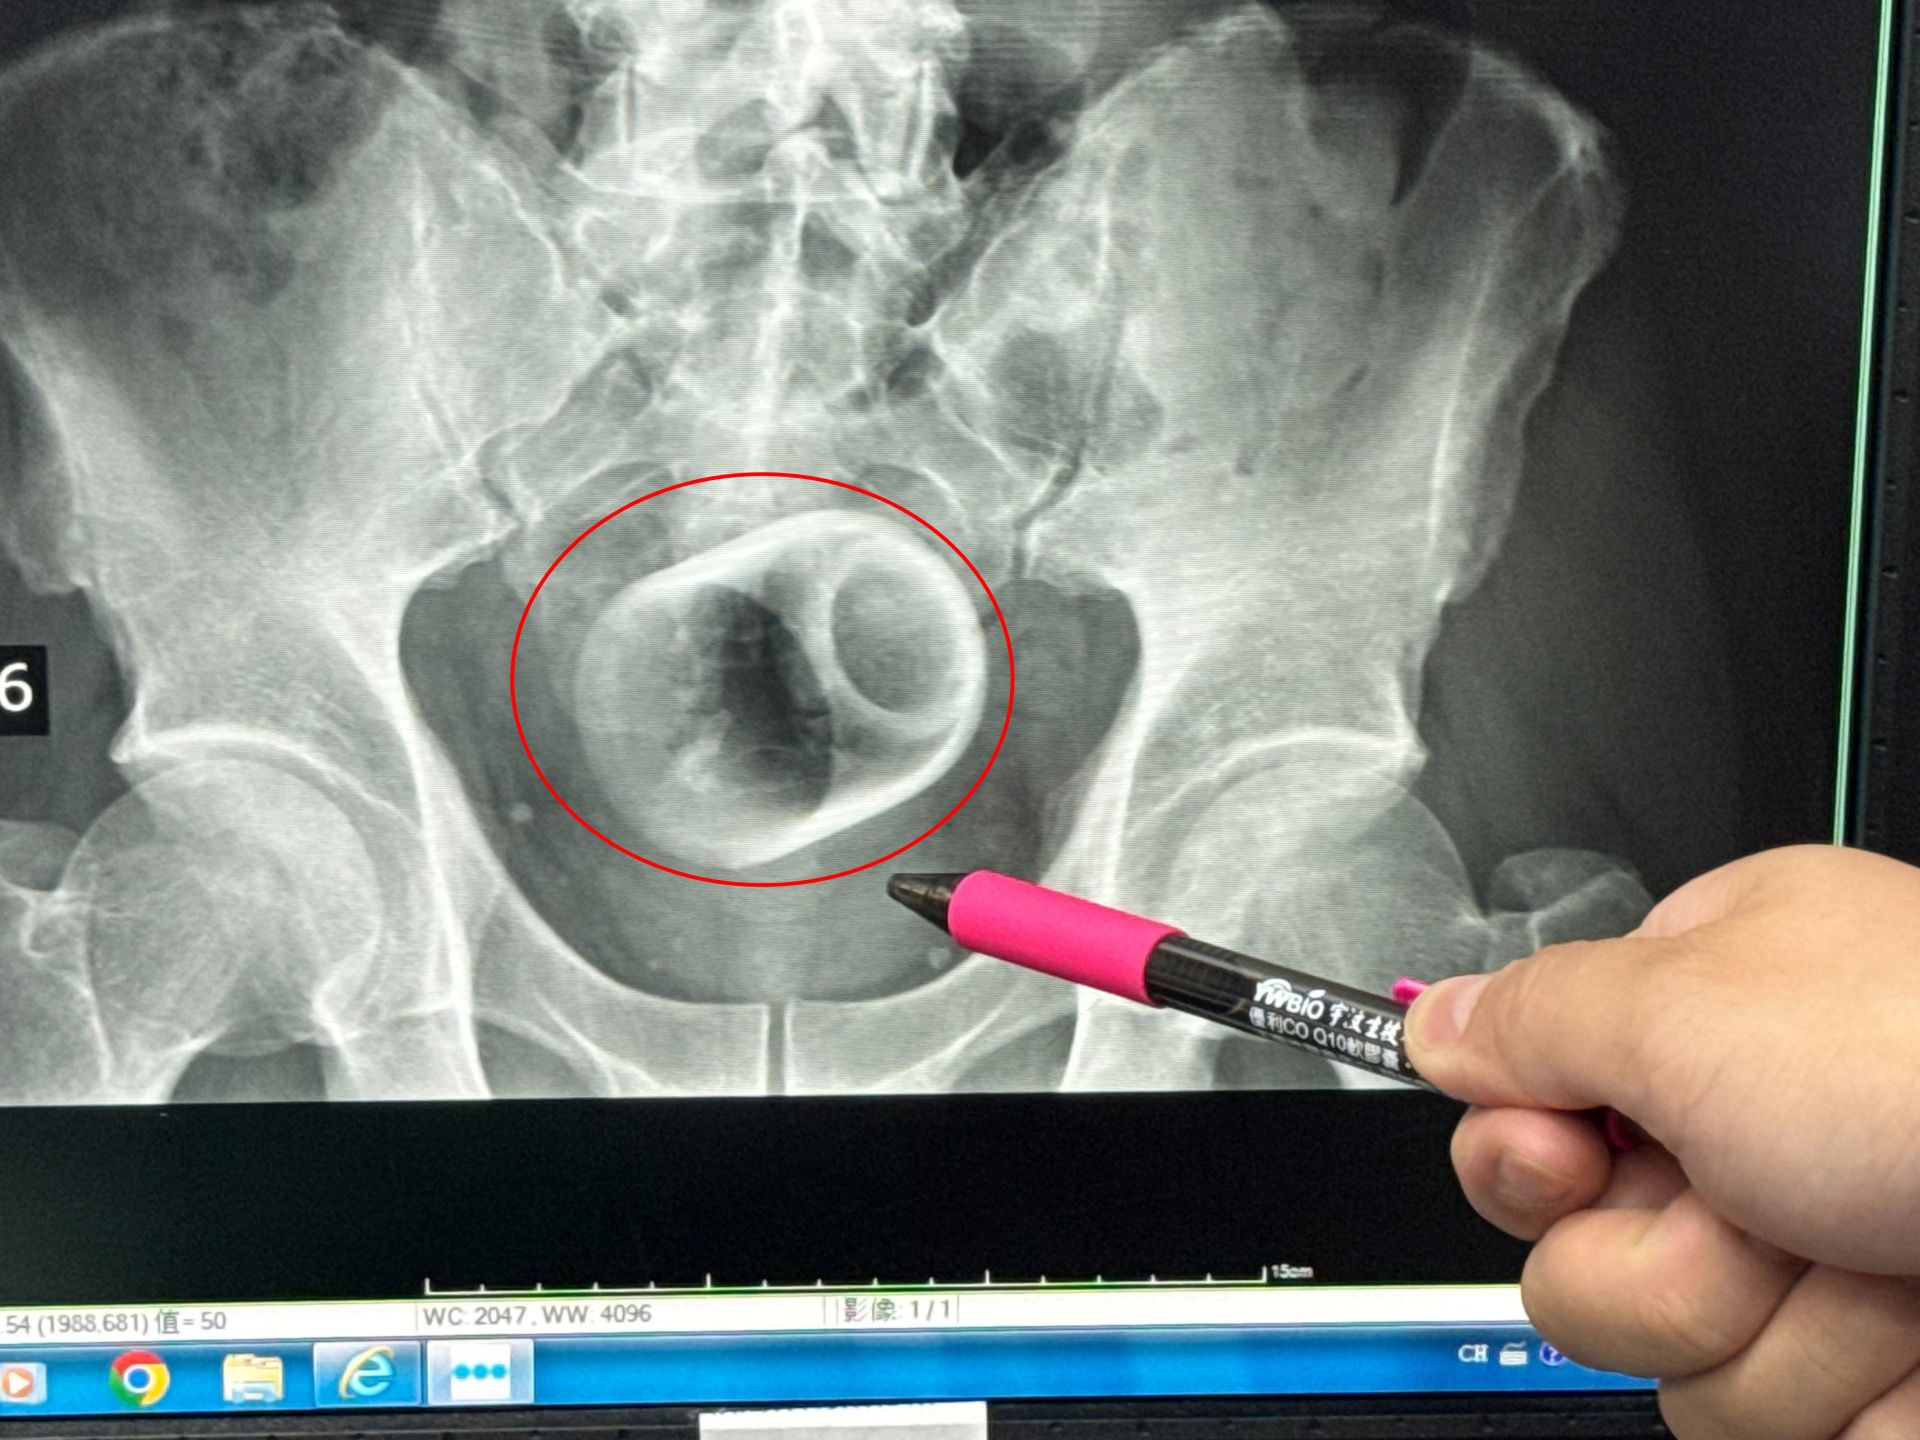

一名男子把陶瓷杯塞進肛門,X光片顯示出杯子放在骨盆腔內,經手術後才取出。大甲李綜合醫院提供

【Lai傳媒 記者爆料網 蔡智銘/台中報導】中部一名男子腹脹三天無法大便,肚子痛到受不了,趕緊到醫院求診,經過X光檢查,醫師驚見患者的肛門竟然塞一個直徑約6公分、高約8公分的陶瓷杯,外科醫師原本要使用器械把杯子夾出來,但杯緣光滑無法施力,杯子全被大腸包住,部分腸子缺血也造成壞死,最後全身麻醉「開腸破肚」的才把杯子取出。

駐診在李綜合醫院的台中榮總外科醫師吳坤達表示,該名患者到院時,自訴三天無法大便非常困擾,害羞不敢提及自己肛門塞了一個杯子,經過X光攝影,看到骨盆腔內有一個杯子,杯口朝下,因此,馬上安排進手術室,要把杯子拿出來。